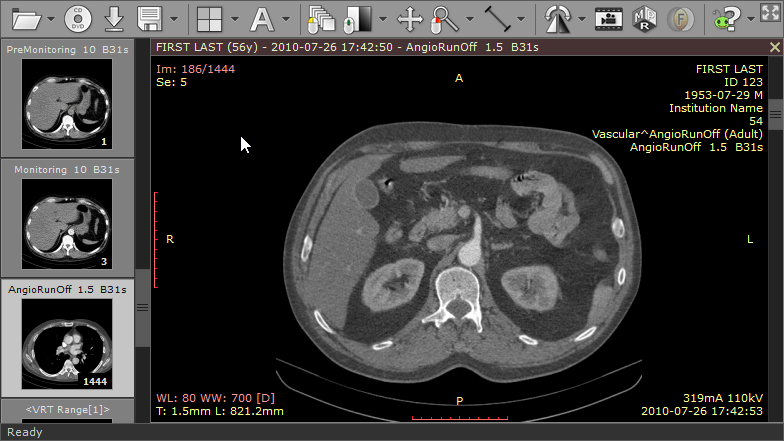

The RadiAnt DICOM image viewer is a simple, fast platform that is compatible with Windows. It offers multiple features, including MPR, MIP, and image fusion. Images can be exported to JPEG, PNG, and other image formats. They can also be copy-pasted directly to presentations and word documents.

The application is just a viewer and does not offer storage space. Their website has a disclaimer explicitly stating that they do not have any certifications, and as such, the product is not intended for diagnostic use. However, it is handy for students and residents for studying medical images and research purposes.

| 3. | RadiAnt | Windows | Not available | Y | Y | Y | Image files, Word and PowerPoint | 5 MB | Intel Multicore/ 2 GB RAM; Resolution 1064x768 | Free version valid for three months only |